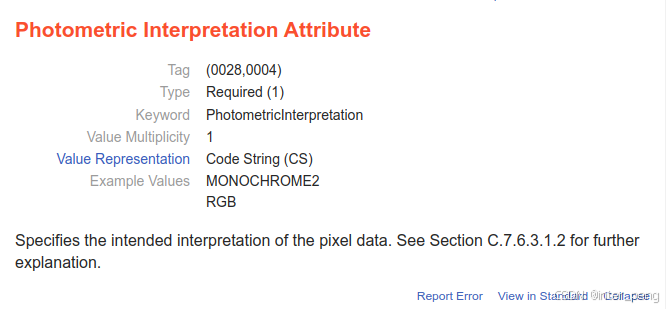

那么,是什么tag来控制这个图像是反片,还是正片呢.是一个名叫:Photometric Interpretation.

关于这个tag的解释,可以从网站上查询得到:

它是一类标签: Required(1),也就是说,医学图像,必须有这个tag, 且有值.

它的枚举值,最常见的是: MONOCHROME2, MONOCHROME1, RGB等.